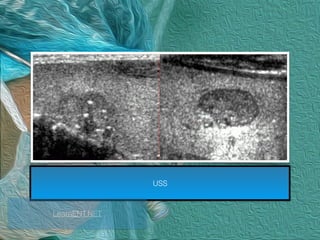

USS

LearnENT.NET

1. Hypoechogenicity

2. Irregular/microlobulated margins

3. Microcalicifications

4. Taller - than - wide

Kim, E.K et al. (2002) New sonographic criteria for recommending fine-needle aspiration biopsy of non-palpable

solid nodules of the thyroid. American Journal of Roentgenology, 178, 687–691.